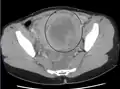

A relatively large submucosal leiomyoma; it fills out the major part of the endometrial cavity.